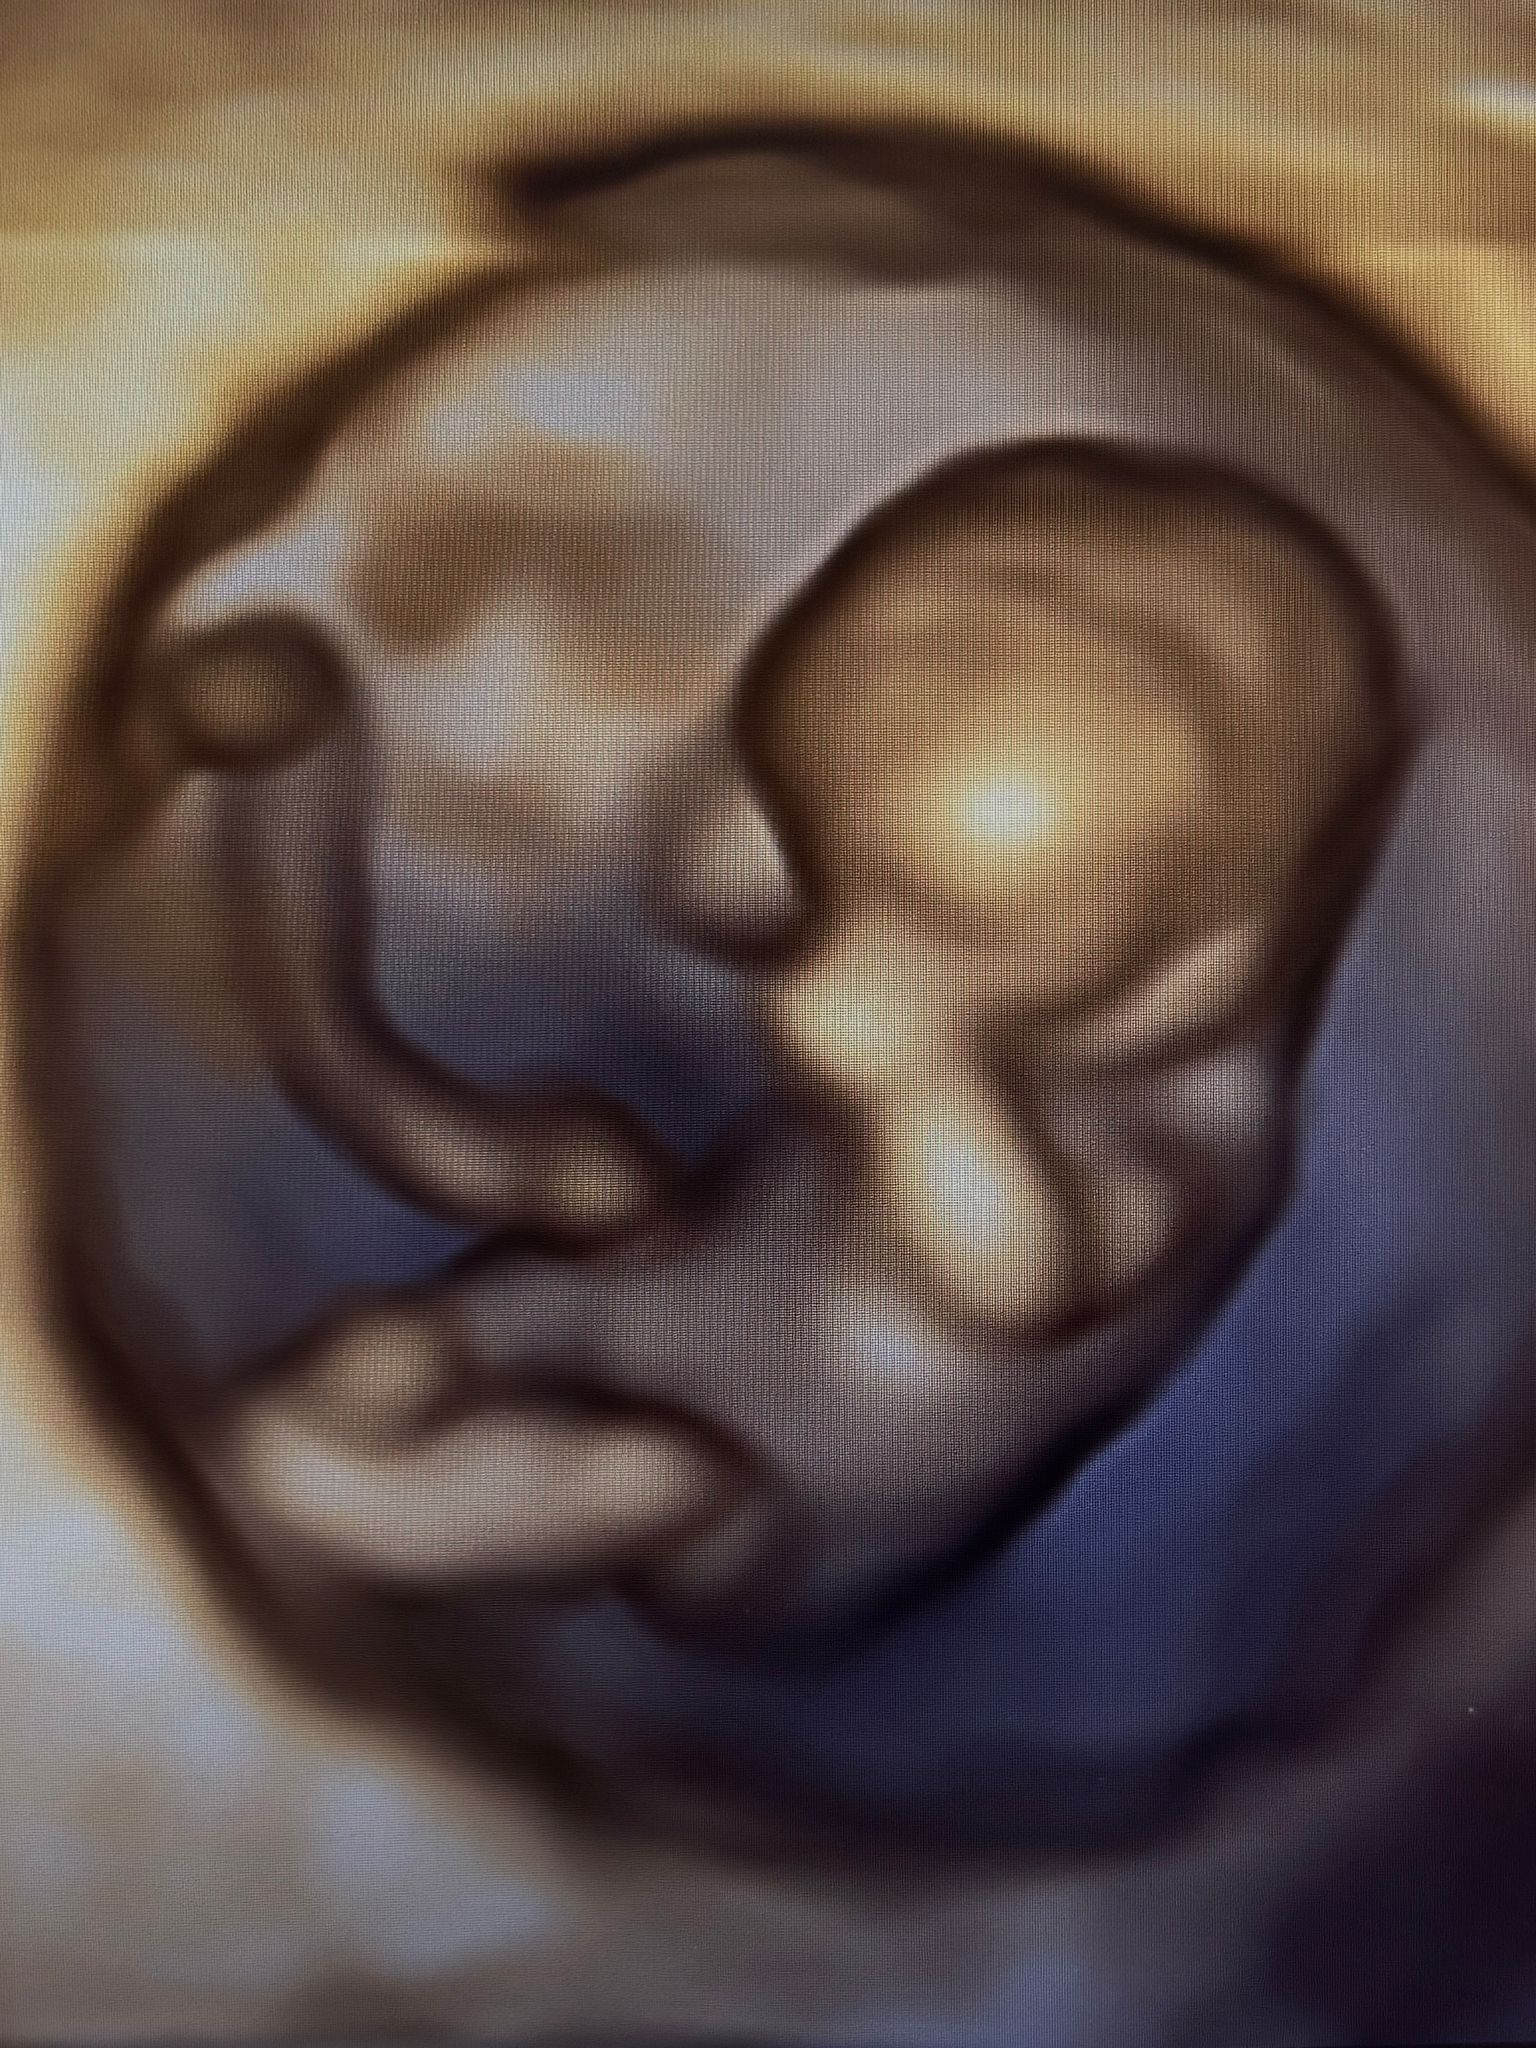

Robię próbę, czy w ogóle da się wstawić zdjęcie 😬 mam taką pamiątkę po wczorajszym USG 🥹

0b5d8dd1-491e-474c-b3e2-8fcac6f39bff.jpeg